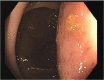

Duplication cysts are rare benign congenital malformations typically identified in children by the age of 2 years. We report a rare case of colonic duplication cyst with dysplasia in an adult. A 32-year-old male was diagnosed with non-specific abdominal symptoms. Abdominopelvic computed tomography scan demonstrated a submucosal cystic lesion in the right colon. He underwent laparoscopic right hemicolectomy. Histopathology showed colonic duplication cyst with low grade dysplasia. He is due for a surveillance colonoscopy in 3 years. Duplication cyst in an adult colon with dysplasia is extremely rare. They are usually present in the terminal ileum. They have non-specific abdominal symptoms or can be asymptomatic. They are often identified incidentally or intraoperatively. Imaging may demonstrate a cystic lesion. Histopathology is required for definitive diagnosis. There are no guidelines or consensus on managing duplication cysts in adults. We recommend an oncological resection of the involved colon. Surveillance with routine colonoscopy is advisable.